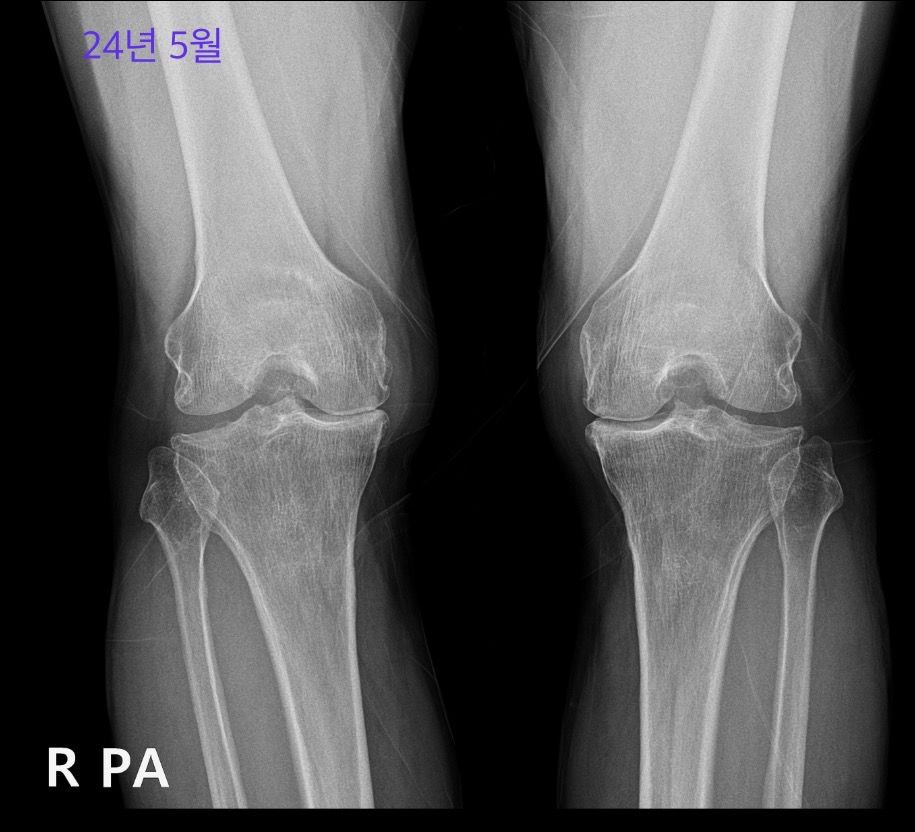

사진은 18년 5월, 18년 12월, 24년 5월입니다.

1. 시간에 따라 악화되었나요?

2. 연도별로 퇴행성 관절염 좌우쪽 각각 몇 기 정도로 보면 될까요?

나이에 상관 없이 고려했을 때에고, 24년 5월 양쪽 무릎 인공관절 수술 소견으로 보여지나요?

• 3번 째 사진

우측 무릎은 18년 5월부터 이미 진행이 많이 되어있는 상태이고 18년 12월에는 관절간격이 조금 더 넓은것처럼 보이지만 현재 grade 4로 보입니다.

좌측은 18년 5월에 우측보다는 가볍지만 grade 3이라고 생각되며 현재 grade 3-4 정도로 보입니다.

인공관절수술은 단순히 병기만 가지고 결정하는게 아니고 증상이 중요합니다.

통증이 얼마나 심하고, 생활은 어느정도 유지 가능하신지를 고려해야겠습니다.

만 67세라면 24년 5월 상태에서 인공관절 수술을 고려할 수 있지만 증상과 기능에 따라 전문의 상담이 필요합니다. 통증이 얼마나 있으신지 혹은 생활은 가능하신지에 따라 달라질 수 있을 것 같아보입니다!